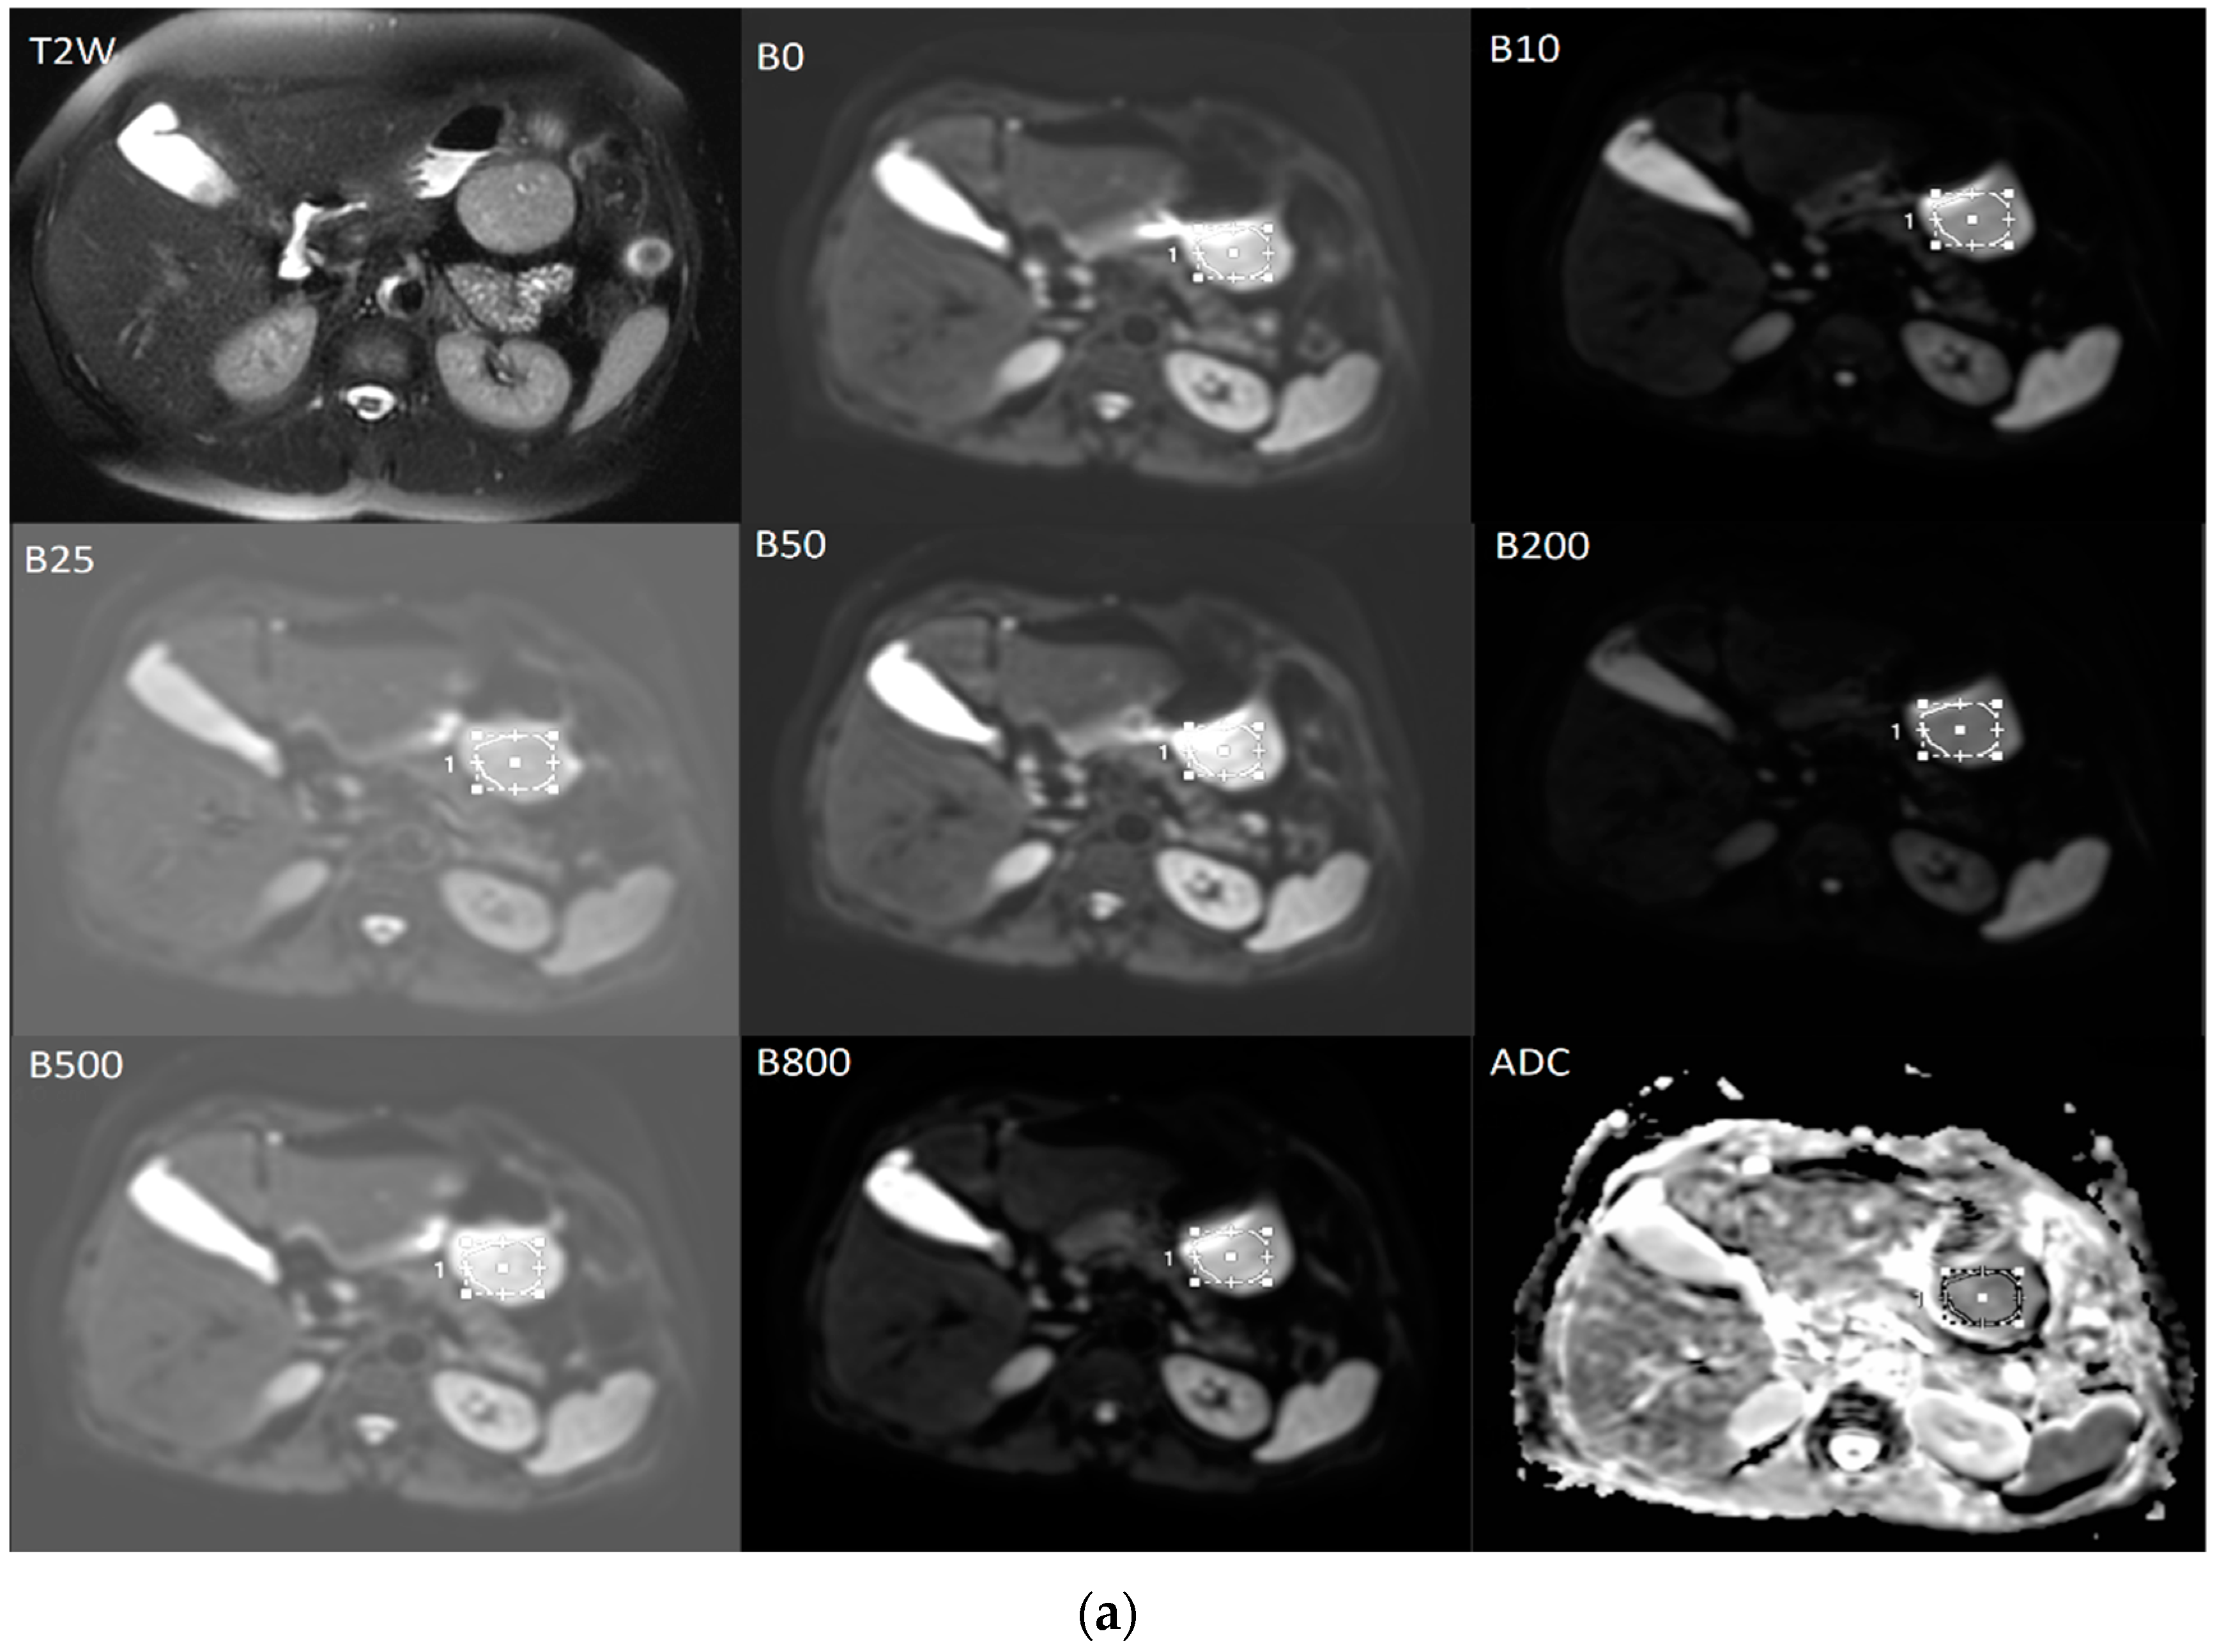

2.4. Processing of DWI Images and Calculation of ADC and IVIM Parameters

The diffusion weighted images were analyzed by a radiologist with 6 years of experience. T2-weighted images were used to help to determining the localization of the tumor more clearly and avoid necrotic areas (Figure 6). On diffusion-weighted images for b = 0, ROI were positioned within the solid tumor region, on three contiguous axial sections at the place of the largest tumor diameter and then automatically copied to all higher b-values parametric maps. Quantitative ADC maps were calculated on voxel-by-voxel basis on the commercial workstation by using the mono-exponential model for the combination of b = 0 and b = 800 [15].

The data for IVIM parameters: true diffusion coefficient (D slow), pseudo-diffusion coefficient (D fast), and perfusion fraction (f) were calculated based on the bi-exponential model by using the MITK Diffusion software, after fitting the signal values from manually located ROIs [15].

The final values of D slow, D fast, f, and the ADC for b = 0 and 800 s/mm² were calculated by averaging the three measurements (Figure 6) [15].

Figure 6. The averaged signal intensity decay and representative IVIM DW images. T2-weighted image in axial view is used for the precise localization of the tumor. DWI with multiple b-values and ROIs (a) followed by signal attenuation curve (b) where true diffusion coefficient (D slow), pseudo-diffusion coefficient (D fast) and perfusion fraction (f) were calculated based on the bi-exponential model.